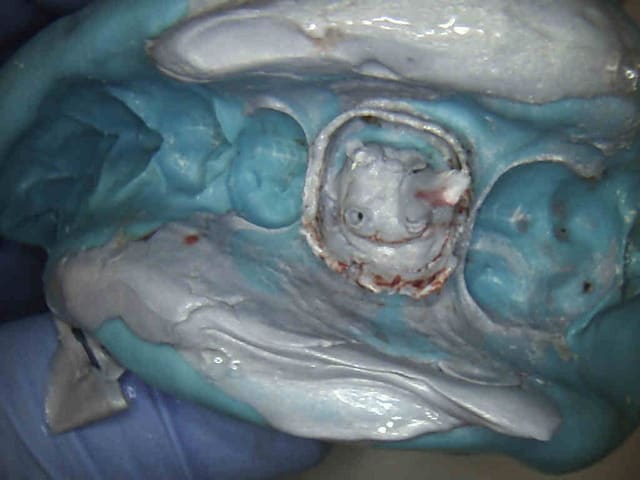

Comment fait tu pour obtenir une éviction gingivale comme celle de tes photos